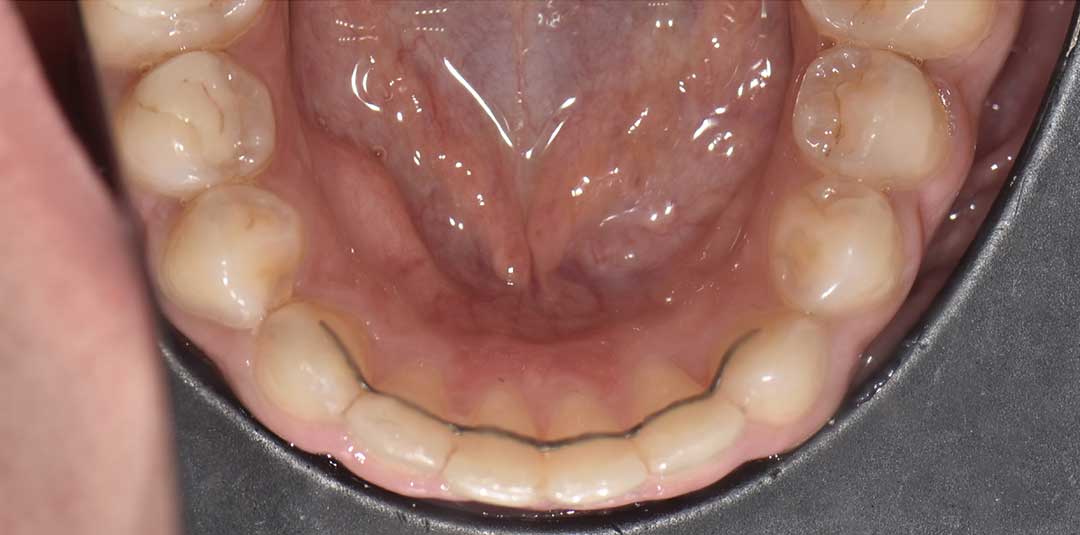

Beautiful Smiles

by Dr. Paolo Bellini